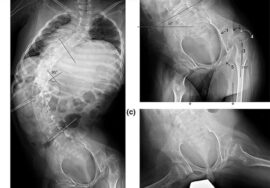

الأشعة الدورية: لتحديد زاوية الانحناء ومتابعة أي تغير.

الفحص السريري المنتظم: لملاحظة الميلان أو تغير مستوى الكتفين والخصر.

الانحناءات الصغيرة في العمود الفقري بين 10 و25 درجة تمثل فرصة ذهبية للتدخل المبكر قبل أن تصبح التغيرات الهيكلية أكثر صعوبة في التصحيح. الدراسات الحديثة تؤكد أن أفضل النتائج تتحقق عند بدء العلاج في هذه المرحلة، سواء من خلال العلاج الطبيعي المخصص، تمارين تقوية العضلات، أو استخدام الحزام التصحيحي عند الحاجة.

الاعوجاج حالة مستمرة ولهذا السب قد تحتاج تدخلًا في مراحل مختلفة من العمر. وبفضل وجود تقنيات التصنيف المعتمدة ، يمكن للأطباء تصميم خطة علاجية مخصصة تضمن تدخلاً جراحيًا عند الضرورة أو العلاج غير الجراحي قبل ذلك، لتفادي الاضطراب في الوظائف التنفسية أو أي أعراض متأخرة. فريقنا المحترف يضم نخبة من الأطباء والمتخصصين الذين يجمعون بين الخبرة والاحترافية لتقديم خطة علاجية غيرر جراحيه شاملة ومخصصة لحالتك، تضمن السيطرة على الانحناء ومنع زيادته.